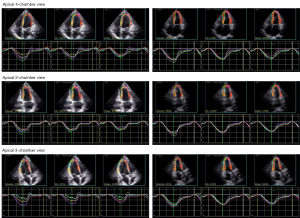

2D STE assessment

Two-dimensional STE was performed using a GE VIVID E95 ultrasound system. Images of the apical four-chamber, apical two-chamber, apical LV long-axis, and LV short-axis views at the basal, papillary, and apical levels were collected within 3–5 cardiac cycles. The software package EchoPAC (version 201 6.3, GE Vingmed Ultrasound) was used to analyze images. Software tracked the endocardium outline and divided the whole ventricle wall into three layers (an endocardial, a mid-myocardial and an epicardial layer). Quantitative myocardial parameters for the global longitudinal strain (GLS) and global circumference strain (GCS) of each layer, and PSD, were obtained. STE data analyses were conducted by two investigators (TL and ZW) who had experience with layer-specific STE and were blind to the clinical data.

The representative images of layer-specific STE’s of one SLE patient and one healthy control are shown in Figures 1 and 2 respectively, and the results of layer-specific STE parameters are displayed in Table 3. Although clinical evidence of cardiac involvement was not detected in SLE patients through routine assessment, an increase in impairment of left ventricular GLS at three layers (whole layer GLS, endocardial GLS, and epicardial GLS) was observed in drug-naïve patients with new-onset SLE, compared with controls (P=0.02, 0.01, 0.04, respectively). Elevation of PSD, which reflects left ventricular dyssynchrony, was also found in SLE patients (P<0.01). In contrast, there was no significant difference in the GCS of the three layers (midmyocardium GCS, endocardium GCS and epicardium GCS) at the basal, papillary, and apical levels between SLE patients and controls (P>0.05, all).